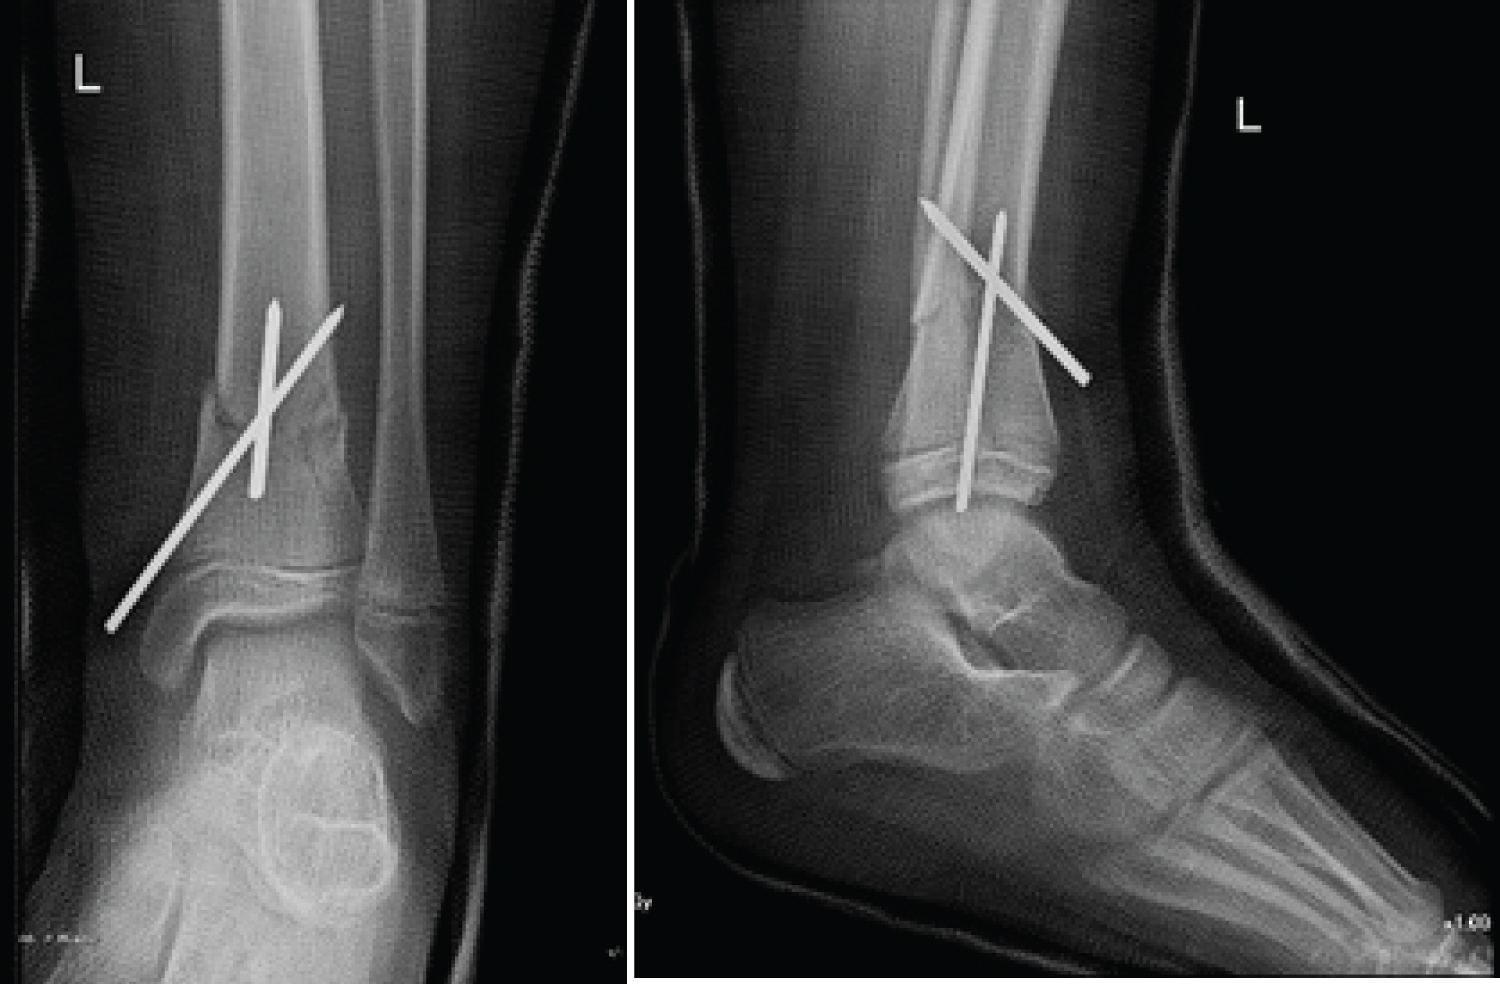

Under general anesthesia, pinning was performed using two retrograde K-wires. The first was intrafocal and was used to achieve the reduction. It was introduced anteriorly and ended on the posterior cortex of the proximal fragment. At the same time, it gave the advantage to adjust and to maintain the reduction in the sagittal plane by its buttress effect on the distal fragment, hence limiting the recurvatum. The second K-wire was introduced medially, distal to the fracture, and ended on the lateral cortex of the proximal fragment to avoid posterior displacement (Figure 4). The K-wires were then cut beneath the skin. No stabilization was done on the fibula. The surgery was followed by a below knee non-weight bearing cast.

Figure 4: Post-operative radiographs showing the anatomical reduction and conservation by intrafocal pining. View Figure 4